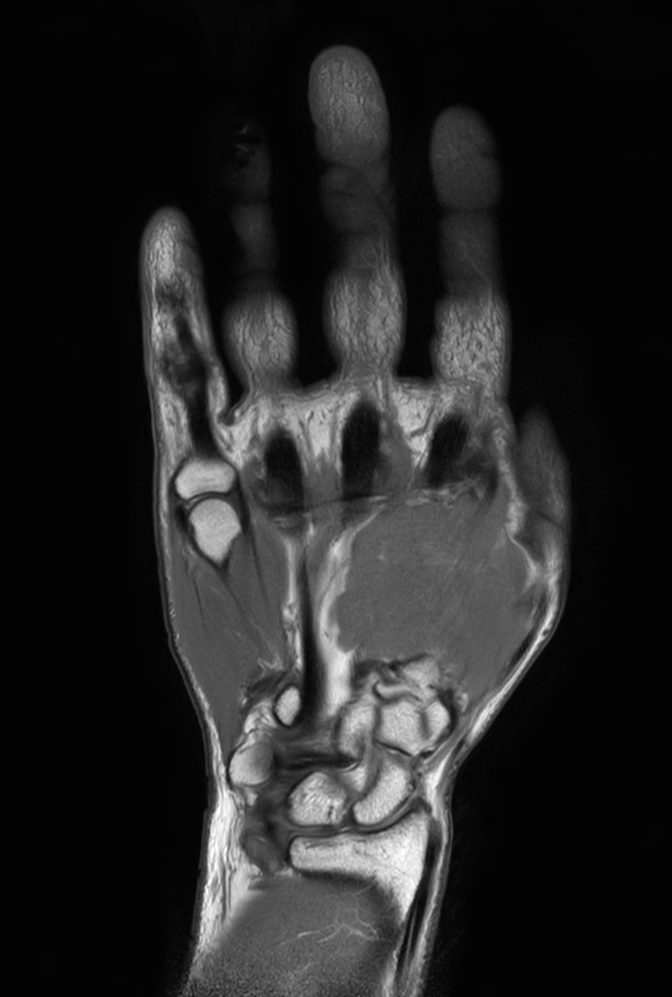

Coronal T1w TSE